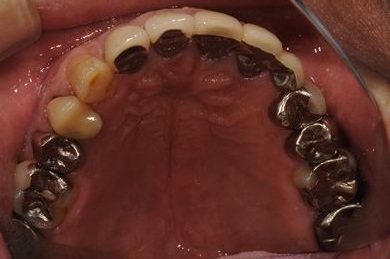

治療前

• 治療前